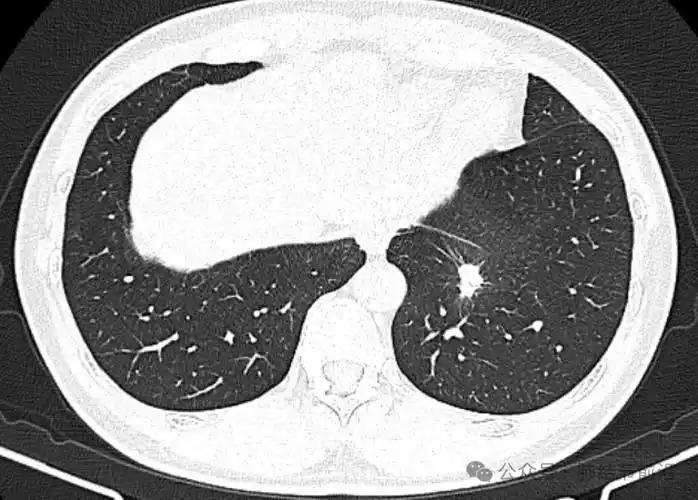

2008年,作家马原患癌,他只做了1次肺部穿刺,就决定放弃任何治疗。跟妻子到云南生活14年后,老天却带走他的小儿子。 2022年, 南糯山的雨季格外漫长。一个阴沉的傍晚, 马原13岁的儿子马格在卫生间突然倒地, 等救护车辗转一个小时赶到山上时, 这场意外已经无法挽回。此后很长一段时间里, 山里的风声在他耳里, 都像是儿子的呼喊。 这个曾在八九十年代叱咤文坛的先锋派作家, 早已把自己藏进大山。很少有人知道, 在丧子之前, 他已经和病魔对峙了十几年。 2008年, 他被查出肺部肿瘤, 穿刺一次就痛得几乎崩溃。医生建议继续检查并尽快治疗, 他却在权衡良恶性的不同结局后, 选择不再做任何进一步手术, 不愿在冷冰冰的时间表里数着日子。 做出这个近乎任性的决定时, 马原已结束上一段婚姻多年。那之前, 他是能连举一百九十多斤杠铃的东北汉子, 也是在辽宁大学中文系沉潜十年、以“叙事圈套”立足文坛的大腕, 和作家皮皮的婚姻一度被视作才子佳人。 病痛与离异让他遍体鳞伤, 直到遇见比自己小二十多岁的退役运动员李小花, 生活才再度亮起来。 小花身上带着阳光, 说话大大咧咧, 完全不同于他笔下的冷峻叙事。她爽快接受表白, 很快跟他领证, 又在他确诊后坚持办了一场婚礼。 婚礼散去的晚上, 小花含着泪说想要一个孩子, 马原答应了。2009年, 马格出生, 这个迟到的儿子让他在阴影中看到了光。 为了陪妻儿久一点, 他跟学校谈妥停课, 带小花先到海南, 戒烟戒酒, 每天沿海骑行, 身上的带状疱疹慢慢结痂脱落。身体好转, 文思复苏, 他写出了《牛鬼蛇神》。2012年, 一家人又来到西双版纳南糯山, 对这里一见钟情。 南糯山姑娘寨有一所废弃小学, 马原把它买下, 花了几年时间盖起九栋房子, 取名“九路马”, 自嘲式地叫它“马堡”。院里种茶种菜, 房间以喜欢的作家命名, 山风一吹, 书页翻动。纪录片《文学的日常》定格下他们一家三口在山林间的日常, 那时没人想到, 这也是某种告别。 在这片茶山里长大的马格, 比同龄人更安静也更敏锐。正规念书不过三年, 成绩却不差。 十三岁的他已经一米八五, 在树林间奔跑, 写下数万字散文与小说, 还写过《我的爸爸叫马原》, 用稚嫩却清澈的笔触打量这个隐居的父亲。镜头里, 他拿着相机拍短视频, 记录雾气缭绕的山谷和鸡犬相闻的院子。 命运的阴影其实早早笼罩过来。马格被发现心脏有问题, 又有人怀疑是马方综合症。李小花想带他去大医院彻查, 马原却本能地抗拒, 总觉得自己当年是在远离医院、回到自然后一点点好起来的, 儿子或许也能靠这样的生活慢慢扛过去。 夫妻俩一边在山中小心照看, 一边又带着孩子四处问医, 在希望与担忧之间反复拉扯。 真正的那一天来得猝不及防。卫生间里闷响一声, 孩子倒下, 山路狭窄, 救护车迟迟不能抵达。等一切归于寂静, 南糯山的云海照旧翻滚, 马堡的窗子照旧透出灯光, 但这个家再也不完整了。 几年后, 马原在悼文里只写思念, 不提原因。他知道, 自己当初相信顺其自然、相信山林能疗伤的选择里, 也有躲避和侥幸。世事无常, 本以为癌症会先带走自己, 却偏偏是儿子先行一步。 此后, 他更加沉入写作, 像是在纸上与马格对话。小花则开始帮助山里那些上学困难的孩子, 把有限的积蓄分到别人家的书包里。对她来说, 这是另一种方式的延续。 从文坛锋芒毕露的先锋作家, 到带病隐居山林的“筑堡人”, 再到白发苍苍的失独父亲, 马原的人生一再被命运改写。 南糯山的风一天天吹过, 他常说, 人的一生就像四季, 有春的萌动, 有夏的丰盛, 也有秋的凋零和冬的寂静。重要的不是逃避哪一季, 而是在每一个当下, 尽量不辜负眼前的人。 马格的离开, 像是一笔被提前收回的幸福贷款。留下来的那个人, 只能在余生里反复偿还, 用更认真地活下去, 来记住那个曾经在山林间奔跑的孩子。